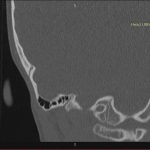

- Diagnosticul traumatismelor de bază de craniu

- Diagnosticul fracturilor:

- Complexe cranio-sinusale

- Complexe cranio-etmoidale

- Complexe cranio-orbitare

- Complexe cranio-faciale